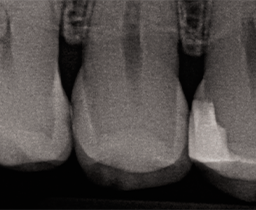

A 32 year-old female patient presented to the practice for her routine examination. The radiographs revealed primary lesions located interproximally (Fig. 1a). The patient was diagnosed with primary caries on tooth #5 DO (Fig. 1b). The clinical objective was to successfully remove caries and restore the tooth while delivering an optimal patient experience.

Fig. 1a Fig. 1b